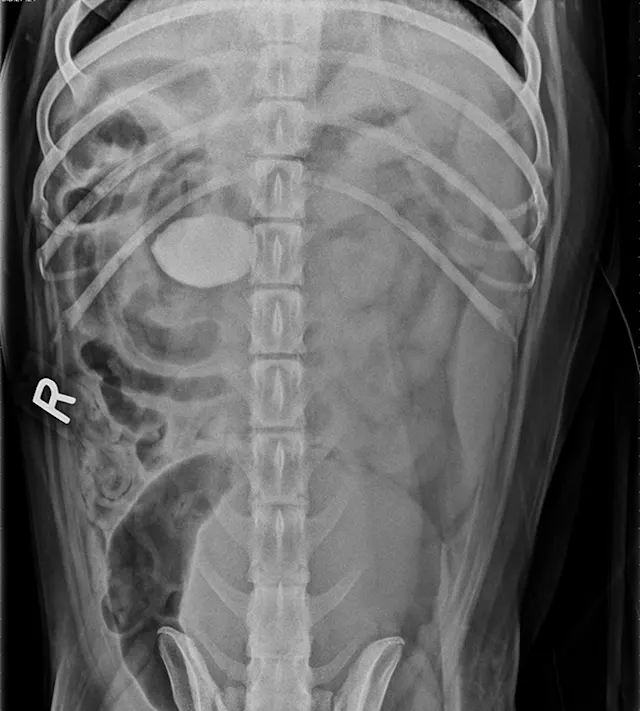

FIGURE 1A

Lateral view. Abdominal radiographs showing a rock foreign body that appears to be located in the small intestine. No small intestinal foreign body could be located on abdominal ultrasound; however, a shadowing foreign object was possibly located in the stomach.